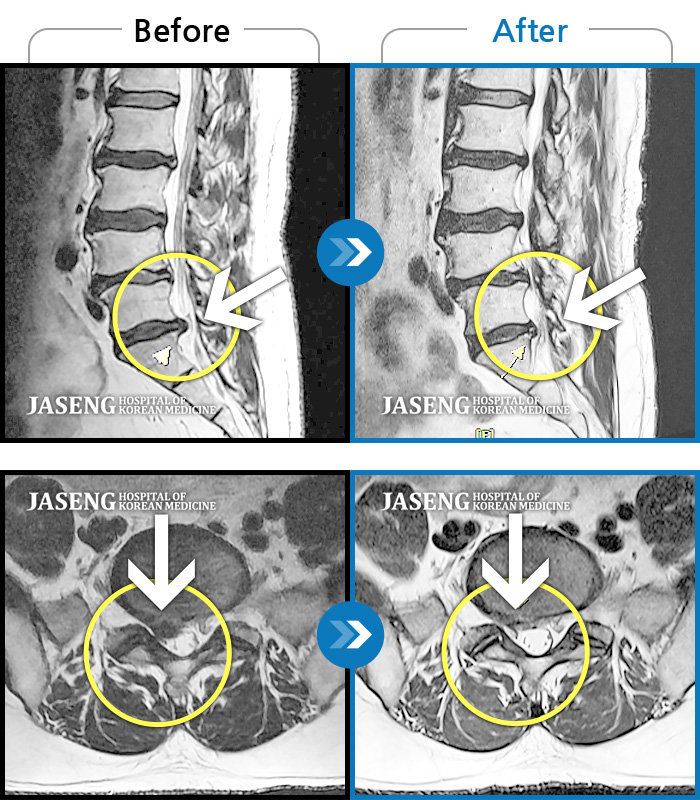

허리디스크

도움받은 사례

광주 · 장영우 원장

좌측 허리 통증으로 허리를 반듯이 펴고 서있기 힘들어 내원하셨습니다.

촬영시기

2024.08.12 ~ 2025.02.26

2025.03.07